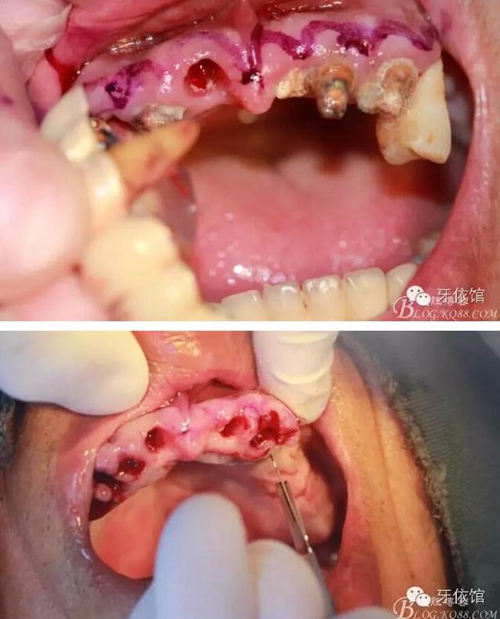

用擴(kuò)孔鉆去除切牙孔內(nèi)神經(jīng)纖維和血管

右上5,6,7牙位內(nèi)提升

切牙壓孔內(nèi)植入植體,扭力50n

將前牙區(qū)取下的骨粉碎

將粉碎的骨填入上頜竇內(nèi)(未加骨粉,全部自體骨)

其余牙位也分別將植體植入